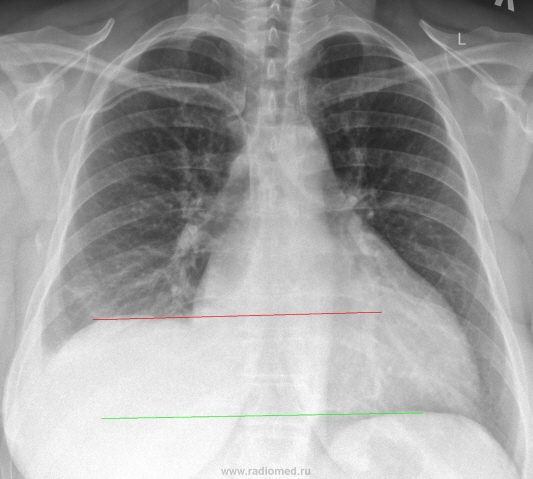

Вчера на дежурстве привозят мне женщину с кардиохирургии, рентген-контроль через 2 часа после плевральной пункции:

Решил взглянуть предыдущий снимочек от 25.11.09г.:

Напрашивается вопрос на основании чего делали пункцию, а на основаннии УЗИ, написали до 6см жидкости, пропунктировали, в действительности получили 1л. жидкости, а вот последствие явно на большее тянет.

На первый вопрос: ///Напрашивается вопрос на основании чего делали пункцию///, отвечу - высокое стояние  купола диафрагмы (в данном случае правого) говорит о возможной жидкости в плевральной полости. Когда УЗИ еще не было, делали латерографию (в данном случае - на правом боку), и если жидкость была, то она была видна уже всем.

Пункцию делали совершенно верно. Над куполом диафрагмы справа значительное количество жидкости - базальный (наддиафрагмальный плеврит). Плохо, весьма плохо, что не произведен правый боковой снимок. Знаю по практике, что в подобных случаях "на боковой" видно "затекание" жидкости в междолевую щель.

Уважаемый Андрей Юрьевич, не было ни какой латерографии, снимок сделан в положении стоя!

Иллюстрация к комментарию выше.

Количество жидкости, И ЭТО ОТЧЕТЛИВО ВИДНО ПО ПРЯМОЙ РЕНТГЕНОГРАММЕ, не может сообветсвовать количеству " в 1 литр", а вот с количеством 2,5 - 3 литра - соглашусь.

Андрей Юрьевич, как "классический рентгенолог", прав на все 100%. На латерограмме было-бы отображение жидкости - выпот не осумкованный - растекся-бы. Если-бы был-бы сделан снимок в положении лёжа (на спине), то в результате растекания жидкости было-бы снижение прозрачности правого лёгочного поля, и сопоставив два снимка - в ортоположении и в положении лежа, вывод о наличии наддиафрагмального плеврита выполз-бы сам собой. По всей видимости "снимок после пункции" и был произведен в положении лёжа, вот и "недопунктированное" количество жидкости растеклось.